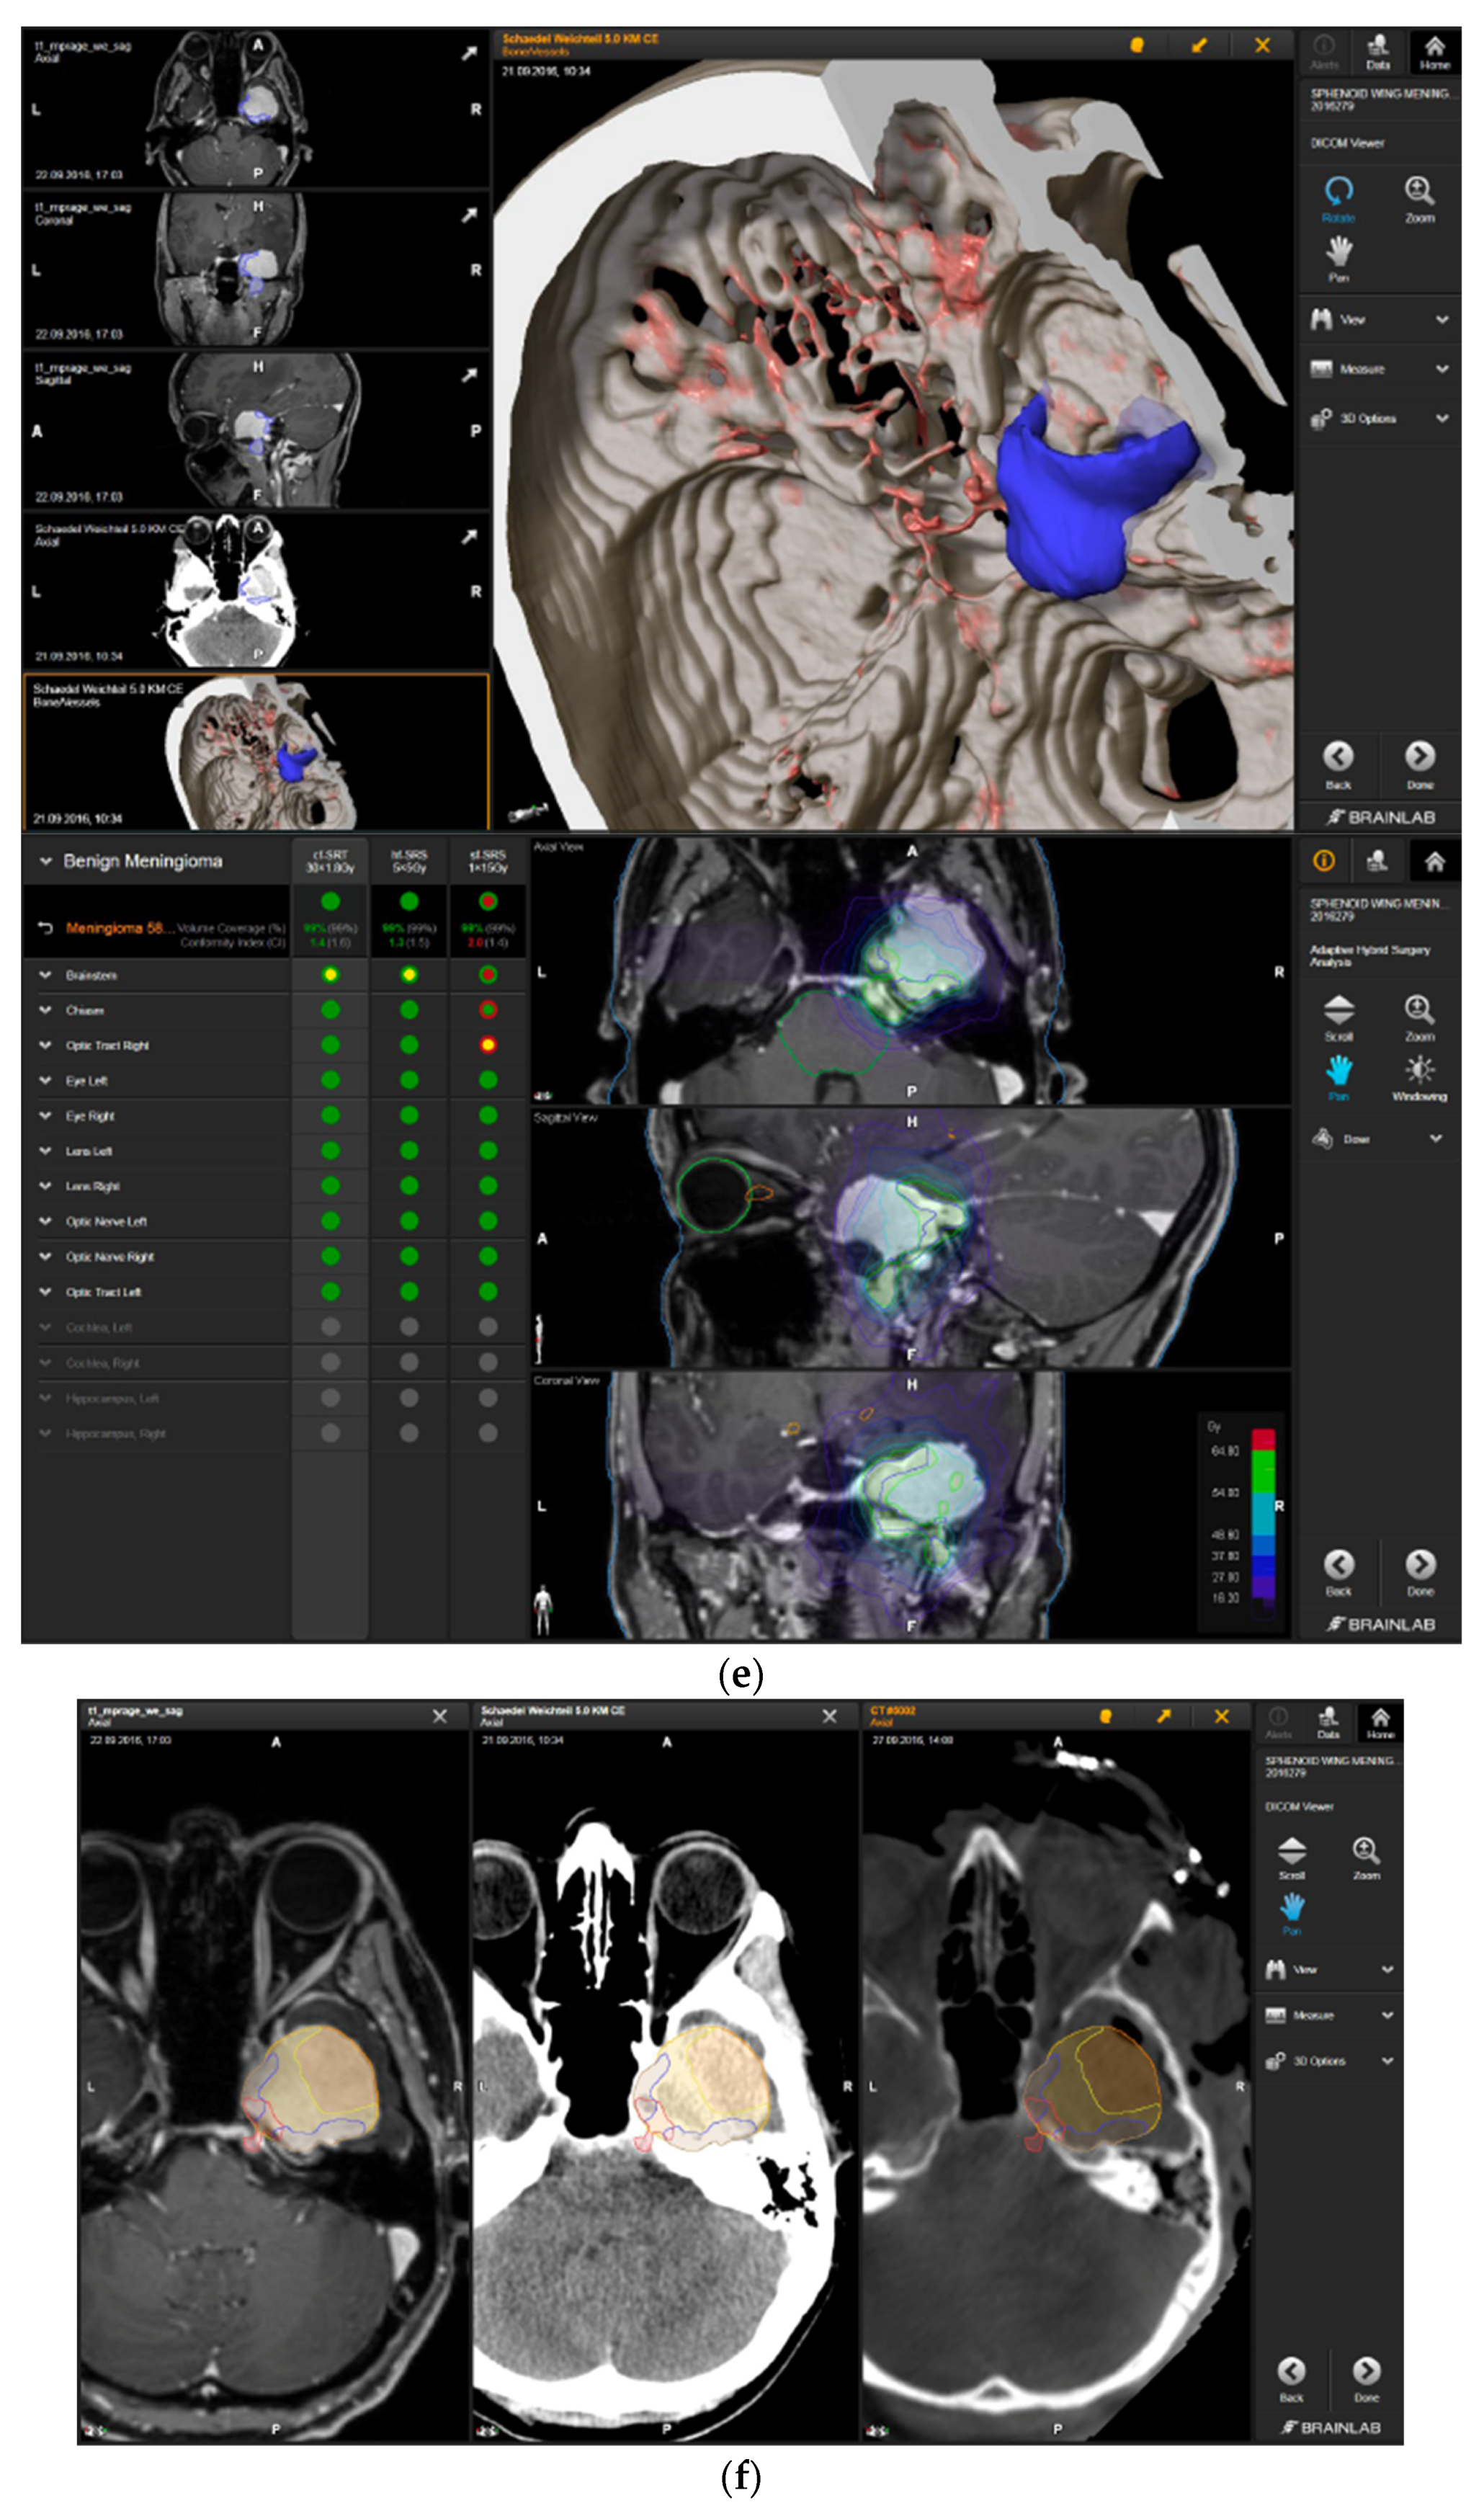

—right hippocampus: unsafe. (g) Overlay of preoperatively estimated and intraoperative effective residual tumor volume in AHSA. (h) Final intraoperative dose constraints after last ISU and data fusion with intraoperative CT. The dose constraints for OARs appeared to improve and were as follows for conventional and hypofractionated radiotherapy:

—brainstem: mean dose is safe, max. dose is marginally safe.

—brainstem: mean dose safe, max. dose unsafe;

—chiasm: mean dose unsafe, max. dose safe;

—right optic tract: mean dose unsafe, max. dose safe. (i) Comparison of pre- and 3 months postoperative MRI for stereotactic radiation planning. The residual tumor was finally treated with hypofractionated radiotherapy (5 × 5 Gy).